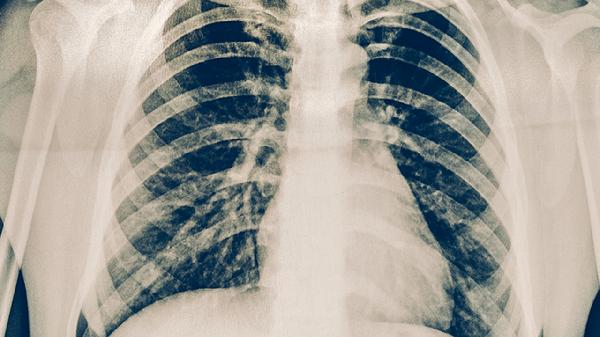

皮肤结核表现为慢性无痛性溃疡、结节或疣状增生,常见类型包括寻常狼疮、疣状皮肤结核等;肺结核典型症状包括咳嗽、咯血、低热、盗汗等全身症状,胸片可见肺部浸润影或空洞。

皮肤结核需通过皮肤活检发现结核性肉芽肿或细菌培养确诊;肺结核诊断依赖痰涂片找抗酸杆菌、结核菌素试验、γ-干扰素释放试验及胸部影像学检查。